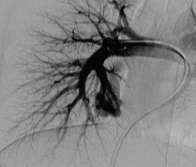

脾偷流综合症

| 腹腔动脉造影,肝动脉供血劣势,脾动脉供血优势 | AVP IV 脾动脉栓塞后,肝动脉供血优势,脾动脉供血劣势 | 栓塞后静脉期 |